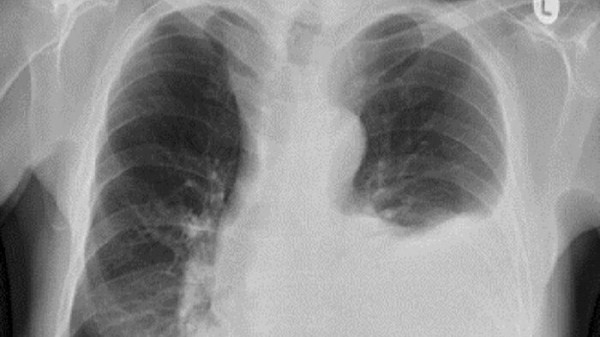

Radiografias de tórax revelaram um quadro de quilotórax, caracterizado pelo acúmulo de líquido leitoso entre as camadas que revestem os pulmões, chamadas de pleuras. Isso acontece quando o sistema linfático, responsável por drenar o excesso de fluidos do corpo, é interrompido.

Exames mais detalhados mostraram um tumor benigno comprimindo os pulmões. O caroço tinha 7 cm e pressionava o ducto torácico — um importante vaso linfático — impedindo que o fluido saísse do corpo.